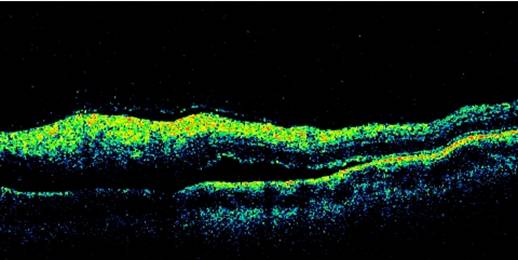

Fourteen men and 11 women were included. The mean age was 25.5 ± 9.9 years. Fifteen patients (60%) had had a previous episode of retinochoroiditis. Active lesions were observed in 16 subjects and scarred lesions in 9 subjects. Active areas appeared as hyperreflective images, which were localized in the retina in 15 cases and in the choroid in 1 case. Partial posterior vitreous detachment with a localized vitritis contiguous to the site of active retinochoroiditis, was observed in 13 cases. Sub-retinal fluid was detected by OCT in 3 cases, but was present on fluorescein angiograms only in 2 of these cases (Figure 1). Scarred areas were characterized by retinal atrophy. The mean retinal thickness at the center of active lesions was 353 ± 98 µm (range 184 - 614 µm), compared to 135 ± 95 µm (range 0 - 338 µm) for scarred lesions (p<0.001).

OCT is safe, non invasive and devoided of any side effects, therefore follow-up measurements are unlimited, while fluorescein angiography is invasive and it carries some risks and side effects in certain subjects. Active toxoplasmic lesions have shown 3 main OCT characteritics:

• A highly reflective intraretinal area corresponding with the area of retinitis.

• A posterior hyaloid thickened and detached over the lesion and contained irregular hyperreflective formation.

• A shadow effect of the underlying choroidal tissue.

Figure 1